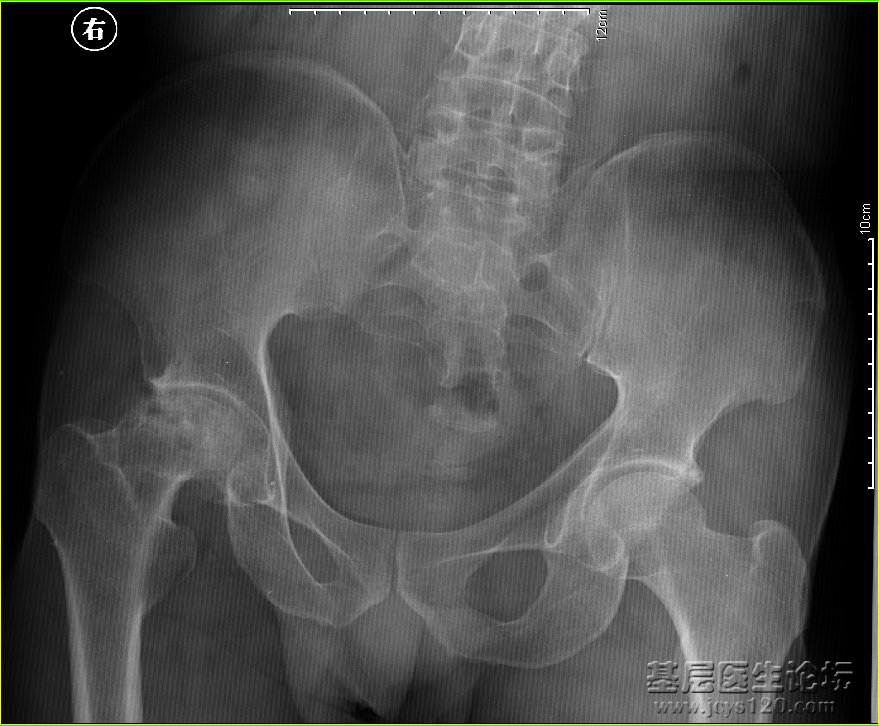

男,52岁,右侧髋部疼痛数年, 阅读全文>